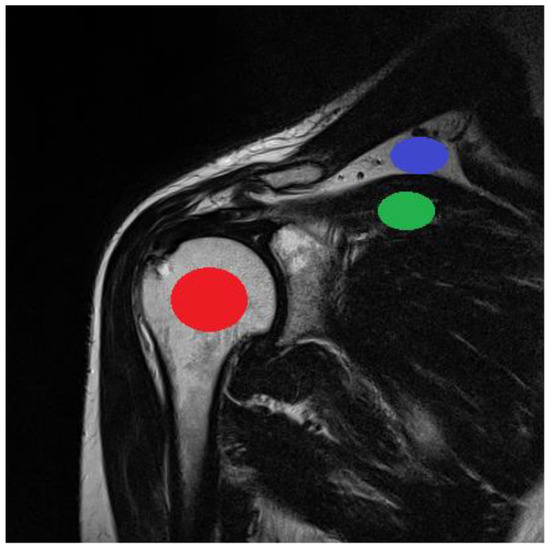

The ROI was visualized and analyzed for every patient on five consecutive layers of each sequence (Figure 5). The average ROI sizes depend on the acquisition matrices; they are presented in Table 2. The position of the ROI in the image was determined by the radiologist. The ROI size was calculated in proportion to the FOV and, consequently, to the image area and size of each tissue tested. The stability of the position and size of the ROI in the image was monitored in all examined cases.

Figure 5.

Position of ROIs used for analyzing different tissue types (bone: red; fat: blue; and muscle: green).